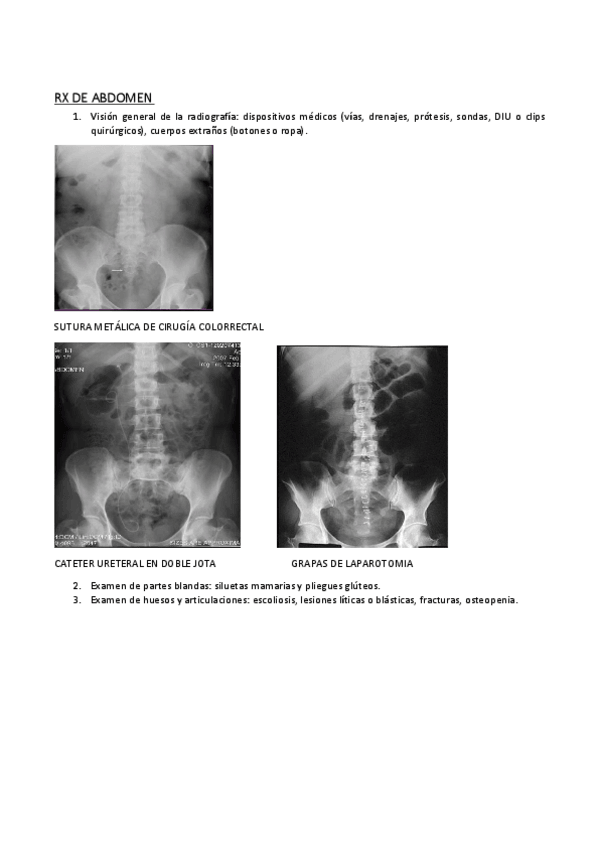

Apuntes - interpretar-la-radiologia-de-abdomen.pdf